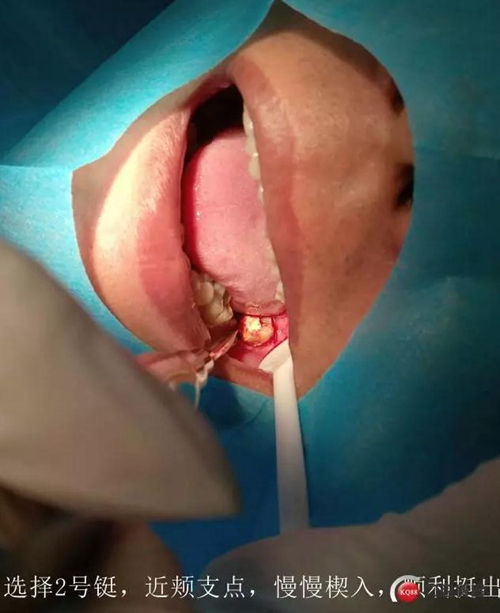

處置:38拔除

盡量囊腫刮除

抗炎治療

討論:對(duì)于這種炎癥感染的囊腫,囊壁基本都不完整的,可視為頜骨囊腫開窗,進(jìn)行二期手術(shù),建議6個(gè)月后復(fù)查曲面。

如果強(qiáng)行一次完整取出,創(chuàng)傷會(huì)較大,神經(jīng)管損傷的可能性非常大,再者根尖區(qū)叩痛提示炎癥,不宜刺激

待頜骨骨壁恢復(fù)到離神經(jīng)管安全距離,再次手術(shù)比較安全。